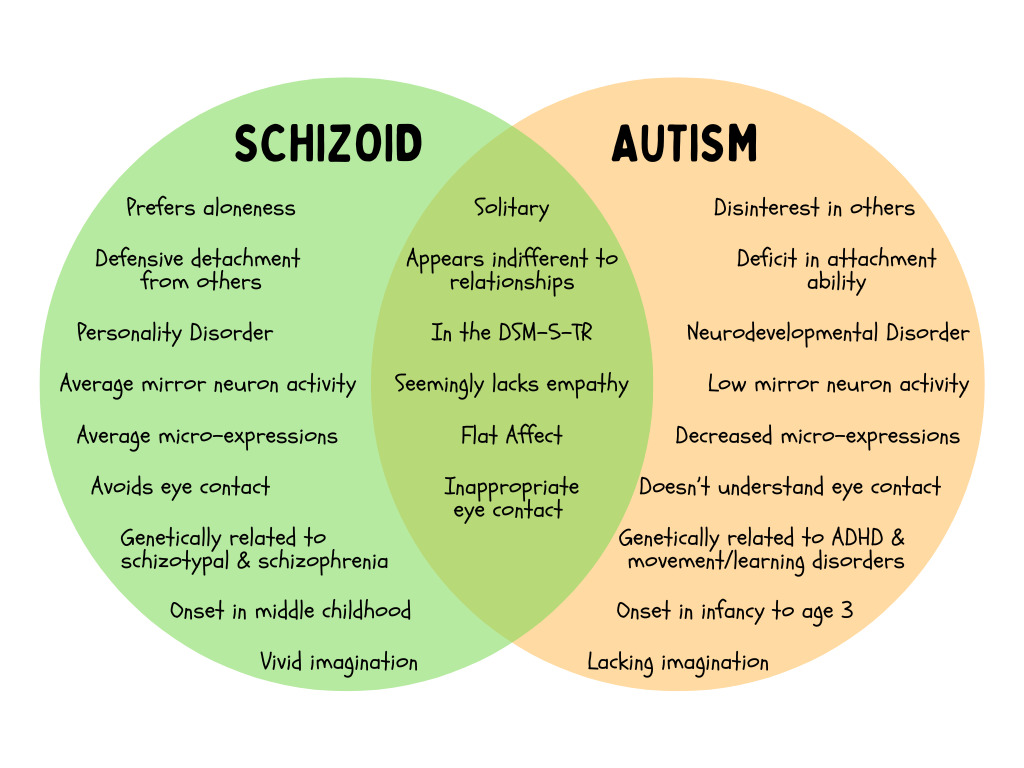

Overlap Between Schizoid and Autism

Schizoid personality disorder and autism spectrum disorder overlap in their observable symptoms. Externally, others can see both those on the autism spectrum and those with schizoid personalities as lacking empathy, having odd communication, and preferring aloneness, as well as being sensitive, emotionally detached, socially disinterested, and cognitively rigid1 2. In fact, one study found a 26% overlap between Asperger’s disorder and schizoid personality disorder - the highest out of all the personality disorders1. However, both are not “allowed” to be diagnosed in the same person, per the DSM3.

The DSM-5-TR

In the DSM-5-TR3, criterion B of schizoid personality disorder specifically says that it “does not occur exclusively during the course of…autism spectrum disorder3.” Then it highlights there can be “great difficulty differentiating” those with schizoid from those with autism, especially if the symptoms are more mild, because both have “a seeming indifference to companionship with others3.” This is followed by one little sentence saying that “autism spectrum disorder may be differentiated by stereotyped behaviors and interests3.” …Not too much information here, so let’s look deeper.

Genetics & Etiology

Before we get to genetics, it’s important to remember that schizoid is associated with schizophrenia in the research. We know that schizophrenia has a strong genetic loading with first degree relatives having an eight- to eleven-fold risk5. We also know that there is substantial heritability for autism spectrum disorder3. Yet, autism and schizophrenia do not show up in the same genetic lines2, which means they are genetically separate. Additionally, schizoid personality disorder has higher comorbidity with schizophrenic and dissociative syndromes, as well as other personality disorders such as, avoidant, schizotypal, and obsessive-compulsive syndromes6. In contrast, autism spectrum disorder has higher comorbidity with other neuro- and/or developmental diagnoses such as ADHD, movement disorders, learning/intellectual disorders, and epilepsy3. Put this all together, and there’s a clear delineation between schizoid as a personality style/disorder and autism spectrum as a neurodevelopmental condition.

Development

Because autism spectrum disorder is a neurodevelopmental condition, it most often presents early in childhood, around the age of 2 or 3, or possibly earlier2. (Of note, while it can present in later development or even adulthood, this is the exception and not the rule). Childhood is also where we see a lack of imaginative play and concrete thinking, as well as stereotyped behaviors3. For example, a child may not engage in social behaviors such as reciprocal eye contact, copying (social smile), or turn taking interactions (i.e. peekaboo, babble conversation). They might not engage in pretend play, only play with a specific toy constantly, and engage in repetitive body movements (i.e. toe walking, flapping hands, arching back, head banging).

Meanwhile, schizoid personality traits emerge around middle childhood2, which is approximately ages 6 to 11. In this stage, focus shifts away from primary attachments towards peers and social groups (i.e. classrooms, sports teams, friend groups). For example, a child might be observed to stare off into space daydreaming instead of engaging in a small group activity with peers. They can actually have difficulty figuring out make-believe from reality because of their strong imagination7. They may withdraw from social interaction and prefer solitary activities.

Mirror Neurons & Facial Expressions

I dug into some research about empathy, mirror neurons, and emotional expression and found something super duper fascinating! One study found that patients with schizophrenia indeed had deficits in observable facial expressions, BUT they had appropriate microexpressions8. So they have normal feelings, but don’t express them. They also found that: others who interacted with patients with schizophrenia decreased their own facial expressiveness and felt more negative experiences (which is perhaps why we overpathologize schizo- dynamics)8. Another study found that actively psychotic individuals had increased mirror neuron activity; schizophrenic individuals had average mirror neuron activity; and individuals on the autism spectrum were found to have little to no mirror neuron activity when observing others9. What this means is that those on the schizoid-schizophrenia spectrum don’t lack emotions and empathy at all, they’re just not expressive. In contrast, those on the autism spectrum have social hardwiring that is not intact. This matches with the research that proposes autism spectrum disorder involves more severe impairment and prognosis2.